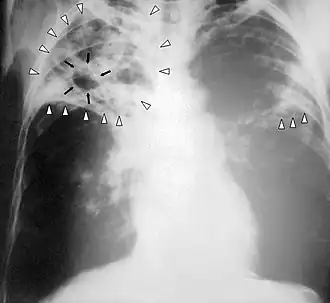

Radiografia ao peito de uma pessoa com tuberculose avançada. As setas brancas assinalam a infeção em ambos os pulmões. As setas pretas assinalam a formação de uma cavidade.

A tuberculose cria cavidades visíveis em radiografias como esta, na parte superior do pulmão direito.

Uma radiografia postero-anterior do tórax é a tradicionalmente feita; outras vistas (lateral ou lordótico) ou imagens de tomografia computadorizada podem ser necessárias.

Em tuberculose pulmonar ativa, infiltrações ou consolidações e/ou cavidades são frequentemente vistas na parte superior dos pulmões com ou sem linfadenopatia (doença nos nódulos linfáticos) mediastinal ou hilar. No entanto, lesões podem aparecer em qualquer lugar nos pulmões. Em pessoas com HIV e outras imunossupressões, qualquer anormalidade pode indicar a tuberculose, ou o raio-x dos pulmões pode até mesmo parecer inteiramente normal.

Em geral, a tuberculose anteriormente tratada aparece no raio-x como nódulos pulmonares na área hilar ou nos lóbulos superiores, apresentando ou não marcas fibróticas e perda de volume. Bronquiectasia (isto é, dilatação dos brônquios com a presença de catarro) e marcas pleurais podem estar presentes.

Nódulos e cicatrizes fibróticas podem conter bacilos de tuberculose em multiplicação lenta, com potencial para progredirem para uma futura tuberculose ativa. Indivíduos com estas características em seus exames, se tiverem um teste positivo de reação subcutânea à tuberculina, devem ser consideradas candidatos de alta prioridade ao tratamento da infecção latente, independentemente de sua idade. De modo oposto, lesões granulares calcificadas (granulomas calcificados) apresentam baixíssimo risco de progressão para uma tuberculose ativa.

Anormalidades detectadas em radiografias do tórax podem sugerir, porém, nunca são exatamente o diagnóstico, de tuberculose. Entretanto, estas radiografias podem ser usadas para descartar a possibilidade de tuberculose pulmonar numa pessoa que tenha reação positiva ao teste de tuberculina mas que não tenha os sintomas da doença.